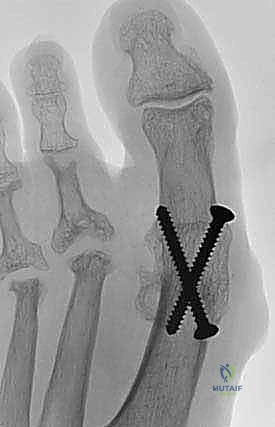

5. التثبيت الداخلي القوي (Internal Fixation)

بمجرد التأكد من الوضعية المثالية، يتم تثبيت العظمتين معاً بقوة باستخدام أدوات التثبيت الطبي (Hardware). هناك عدة تقنيات يستخدمها الدكتور هطيف بناءً على حالة العظم:

* المسامير المتقاطعة (Crossed Screws): استخدام مسمارين أو ثلاثة من التيتانيوم لتوليد ضغط قوي بين العظمتين.

* الشريحة والمسامير (Plate and Screws): وضع شريحة معدنية صغيرة على السطح العلوي للمفصل وتثبيتها بمسامير، وغالباً ما يرافقها مسمار ضغط داخلي. هذه التقنية توفر ثباتاً استثنائياً وتسمح بالتحميل المبكر للوزن.